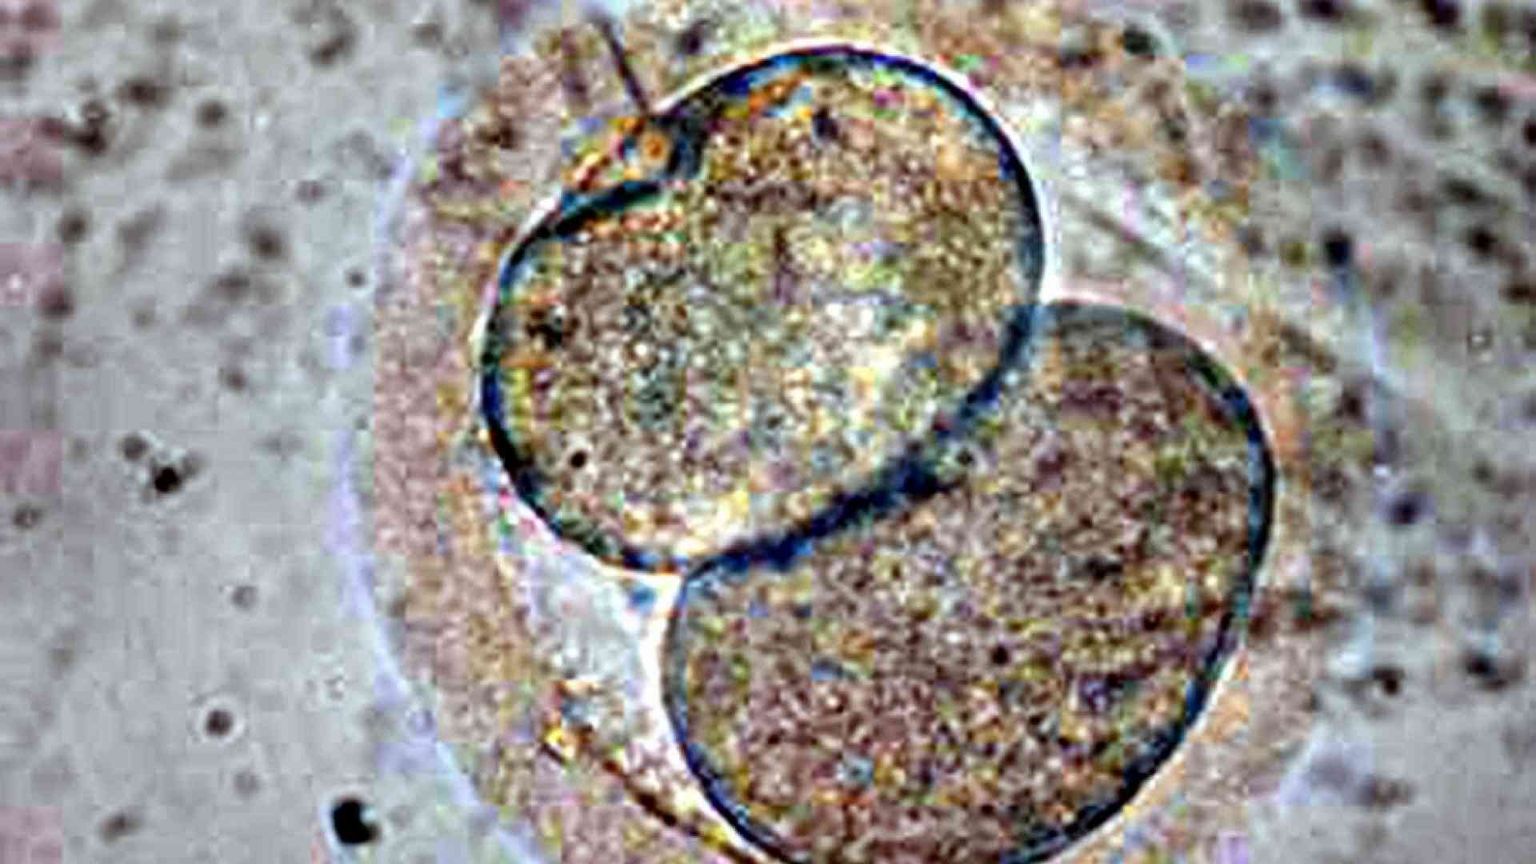

Sono sposati e decidono di ricorrere alla Procreazione medicalmente assistita (Pma) per poter avere un figlio. Un percorso complesso e che vede fallire un primo tentativo di impianto. Altri embrioni vengono però congelati, in attesa di un nuovo tentativo. Nel frattempo, però, lui decide di porre fine al matrimonio, ma lei non vuole rinunciare a quelle "vite in provetta" e al sogno di diventare madre. Così si rivolge ad un tribunale. Che le dà ragione: può impiantare gli embrioni, nonostante la separazione e la contrarietà dell'ex marito.

Se esistono embrioni congelati, prodotti da una coppia, questi possono essere impiantati tempo dopo nell’utero della donna con il solo consenso di questa. E anche contro la volontà dell’uomo di cui portano il corredo genetico.

Il problema, sotto il profilo oggettivo, ha iniziato a esistere con la sentenza 151/2009 della Corte Costituzionale, che – modificando la legge 40 – ha iniziato a permettere il congelamento degli embrioni. Fino a quel momento, infatti, la norma prevedeva che si potessero fecondare fino a un massimo di tre ovociti, i quali avrebbero dovuto essere simultaneamente impiantati nell’utero della donna. Era infatti questo il principio vigente prima della decisione della Consulta: una volta ottenuto, ogni embrione avrebbe dovuto essere messo nelle condizioni di nascere.

Intanto, però, degli embrioni erano stati crioconservati. "Ci ho pensato tanto, ma quegli embrioni creati in un contesto di amore - afferma - io non me la sono sentita di abbandonarli in una provetta, e ho deciso almeno di provare a metterli al mondo lo stesso, anche come donna single. Mi sono rivolta agli avvocati Baldini e Zema e grazie al loro aiuto anche il giudice ha capito che il mio progetto era serio". Il punto, conclude, "è che credo non sia giusto venire meno alle proprie responsabilità genitoriali, e per quello che mi riguarda sono contenta che il giudice abbia riconosciuto a me ed a nostro figlio, per ora solo concepito, il diritto almeno di provarci".